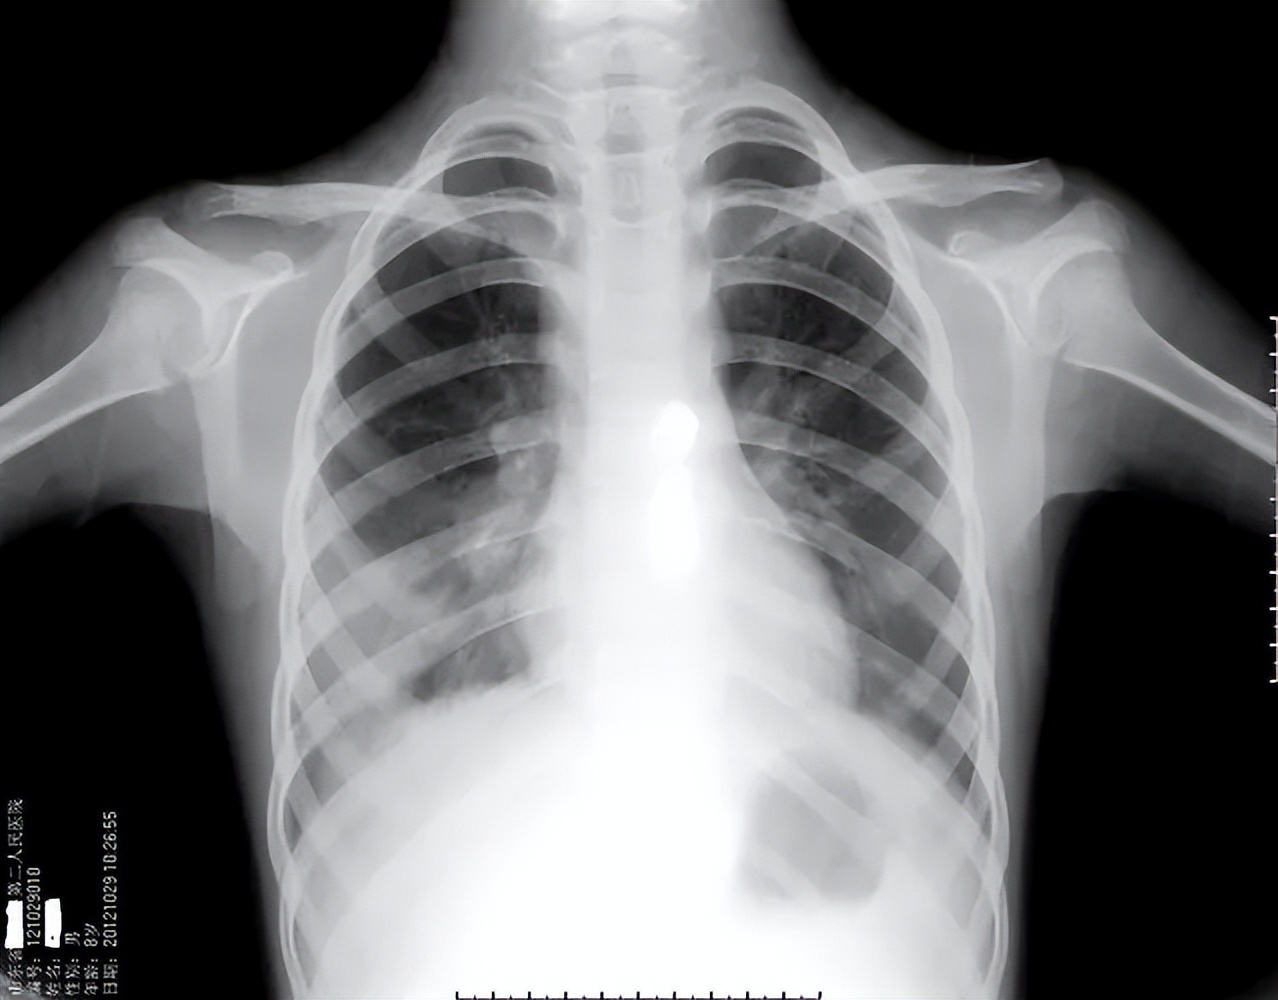

一个小时后,田女士拿着检查报告回来了,医生简单的看了看X光的结果, 田女士的右肺下叶有钝性改变,也就是有积液,然后血常规检查提示有感染,医生初步判断这可能是细菌性肺炎导致的,于是给予头孢、加替沙星治疗。

无奈之下,医生就给田女士 做了心电图、心脏彩超然后又补充了肺部CT检查,这次的检查结果就严重多了,田女士的心电图显示T波发生了改变,而且右肺下叶有实变影,胸腔积液引起了不是那么严重的肺不张。

终于水落石出!肺动脉造影提示田女士的 肺动脉主干出现了不完全栓塞,右下肺动脉栓塞严重,医生按照经验又给田女士做了双下肢的血管彩超,未发现明显的血栓,排除了双下肢静脉血栓的问题。